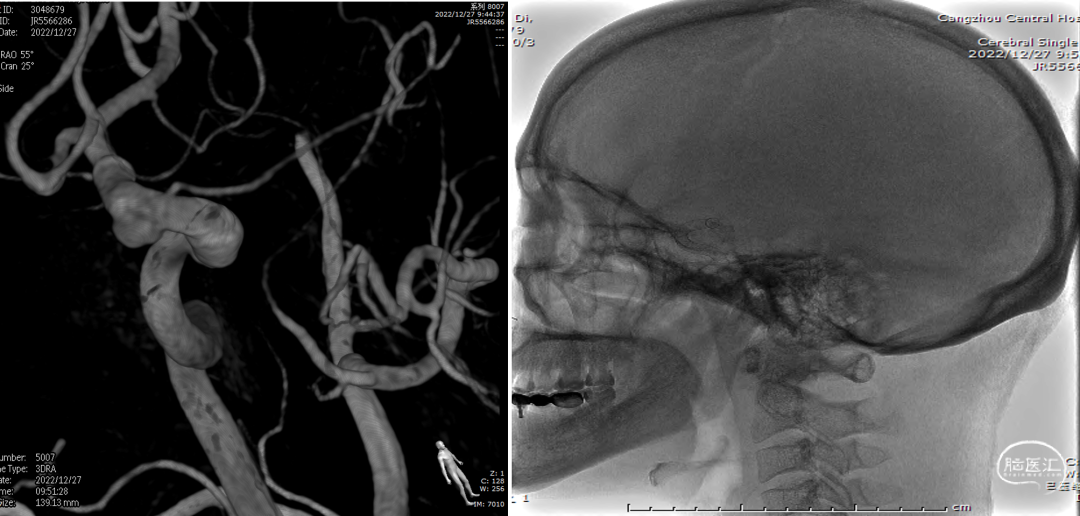

术后复查右颈内动脉造影(2022-12-27)

术后复查右颈内动脉3D重建

复查左颈内动脉造影(2022-12-27)

术后3D重建

术后3D图像及透视

术前、术后3D图像对比